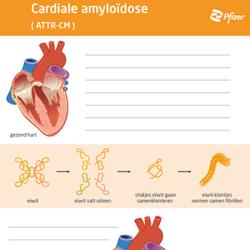

Scheurblok cardiale amyloïdose

Bestellen